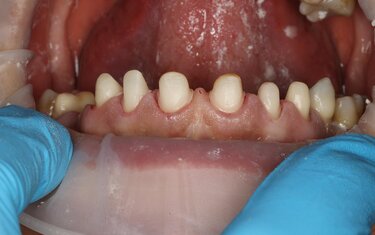

Figure 9: The patient’s teeth were prepped for a 4-unit zirconia bridge on teeth #11-#14 and single full-contour crowns on teeth #6-#10. The preps were scanned and the bridge and individual crowns designed in CAD software.